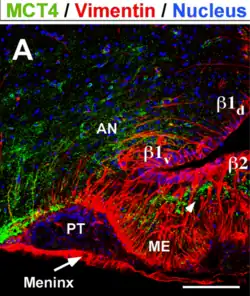

En la morfogénesis, el suelo del hipotálamo forma el infundíbulo, una evaginación digitiforme y hueca, a partir de la que se desarrollan dos estructuras: la neurohipófisis y la eminencia media. Esta última es una zona de contacto neurohemático, que forma una interfaz funcional entre el hipotálamo y el lóbulo anterior de la hipófisis.[5]

- ↑ Cortés-Campos C., Elizondo R., Llanos P., Uranga R.M., Nualart F., García M.A. (2011). «MCT Expression and Lactate Influx/Efflux in Tanycytes Involved in Glia-Neuron Metabolic Interaction». PLoS ONE 6 (1): e16411. doi:10.1371/journal.pone.0016411. Consultado el 10 de enero de 2021.